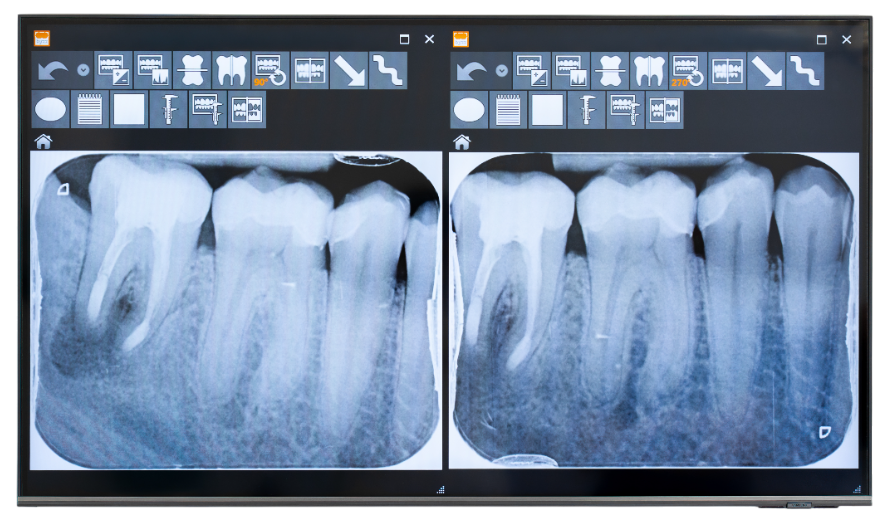

Zwei digitale Röntgenaufnahmen von Backenzähnen auf einem Monitor. Die Bilder zeigen Zahnwurzeln, Wurzelkanäle und den umgebenden Kieferknochen zur Beurteilung des Zahnzustands.

Vorher

Nachher